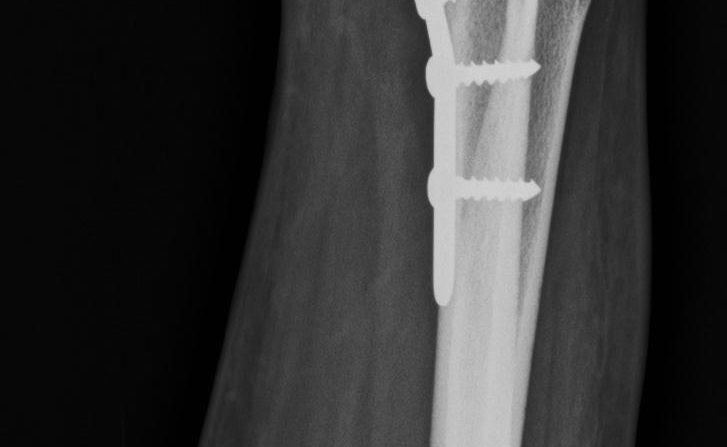

Dr Kamran Saeed is a well known and extremely experienced orthopedic and trauma surgeon of Lahore, Pakistan .